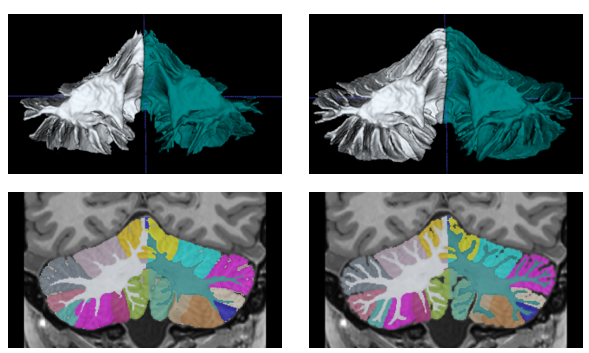

This paper introduces a novel multimodal and high-resolution human brain cerebellum lobule segmentation method. Unlike current tools that operate at standard resolution ($1 \text{ mm}^{3}$) or using mono-modal data, the proposed method improves cerebellum lobule segmentation through the use of a multimodal and ultra-high resolution ($0.125 \text{ mm}^{3}$) training dataset. To develop the method, first, a database of semi-automatically labelled cerebellum lobules was created to train the proposed method with ultra-high resolution T1 and T2 MR images. Then, an ensemble of deep networks has been designed and developed, allowing the proposed method to excel in the complex cerebellum lobule segmentation task, improving precision while being memory efficient. Notably, our approach deviates from the traditional U-Net model by exploring alternative architectures. We have also integrated deep learning with classical machine learning methods incorporating a priori knowledge from multi-atlas segmentation, which improved precision and robustness. Finally, a new online pipeline, named DeepCERES, has been developed to make available the proposed method to the scientific community requiring as input only a single T1 MR image at standard resolution.